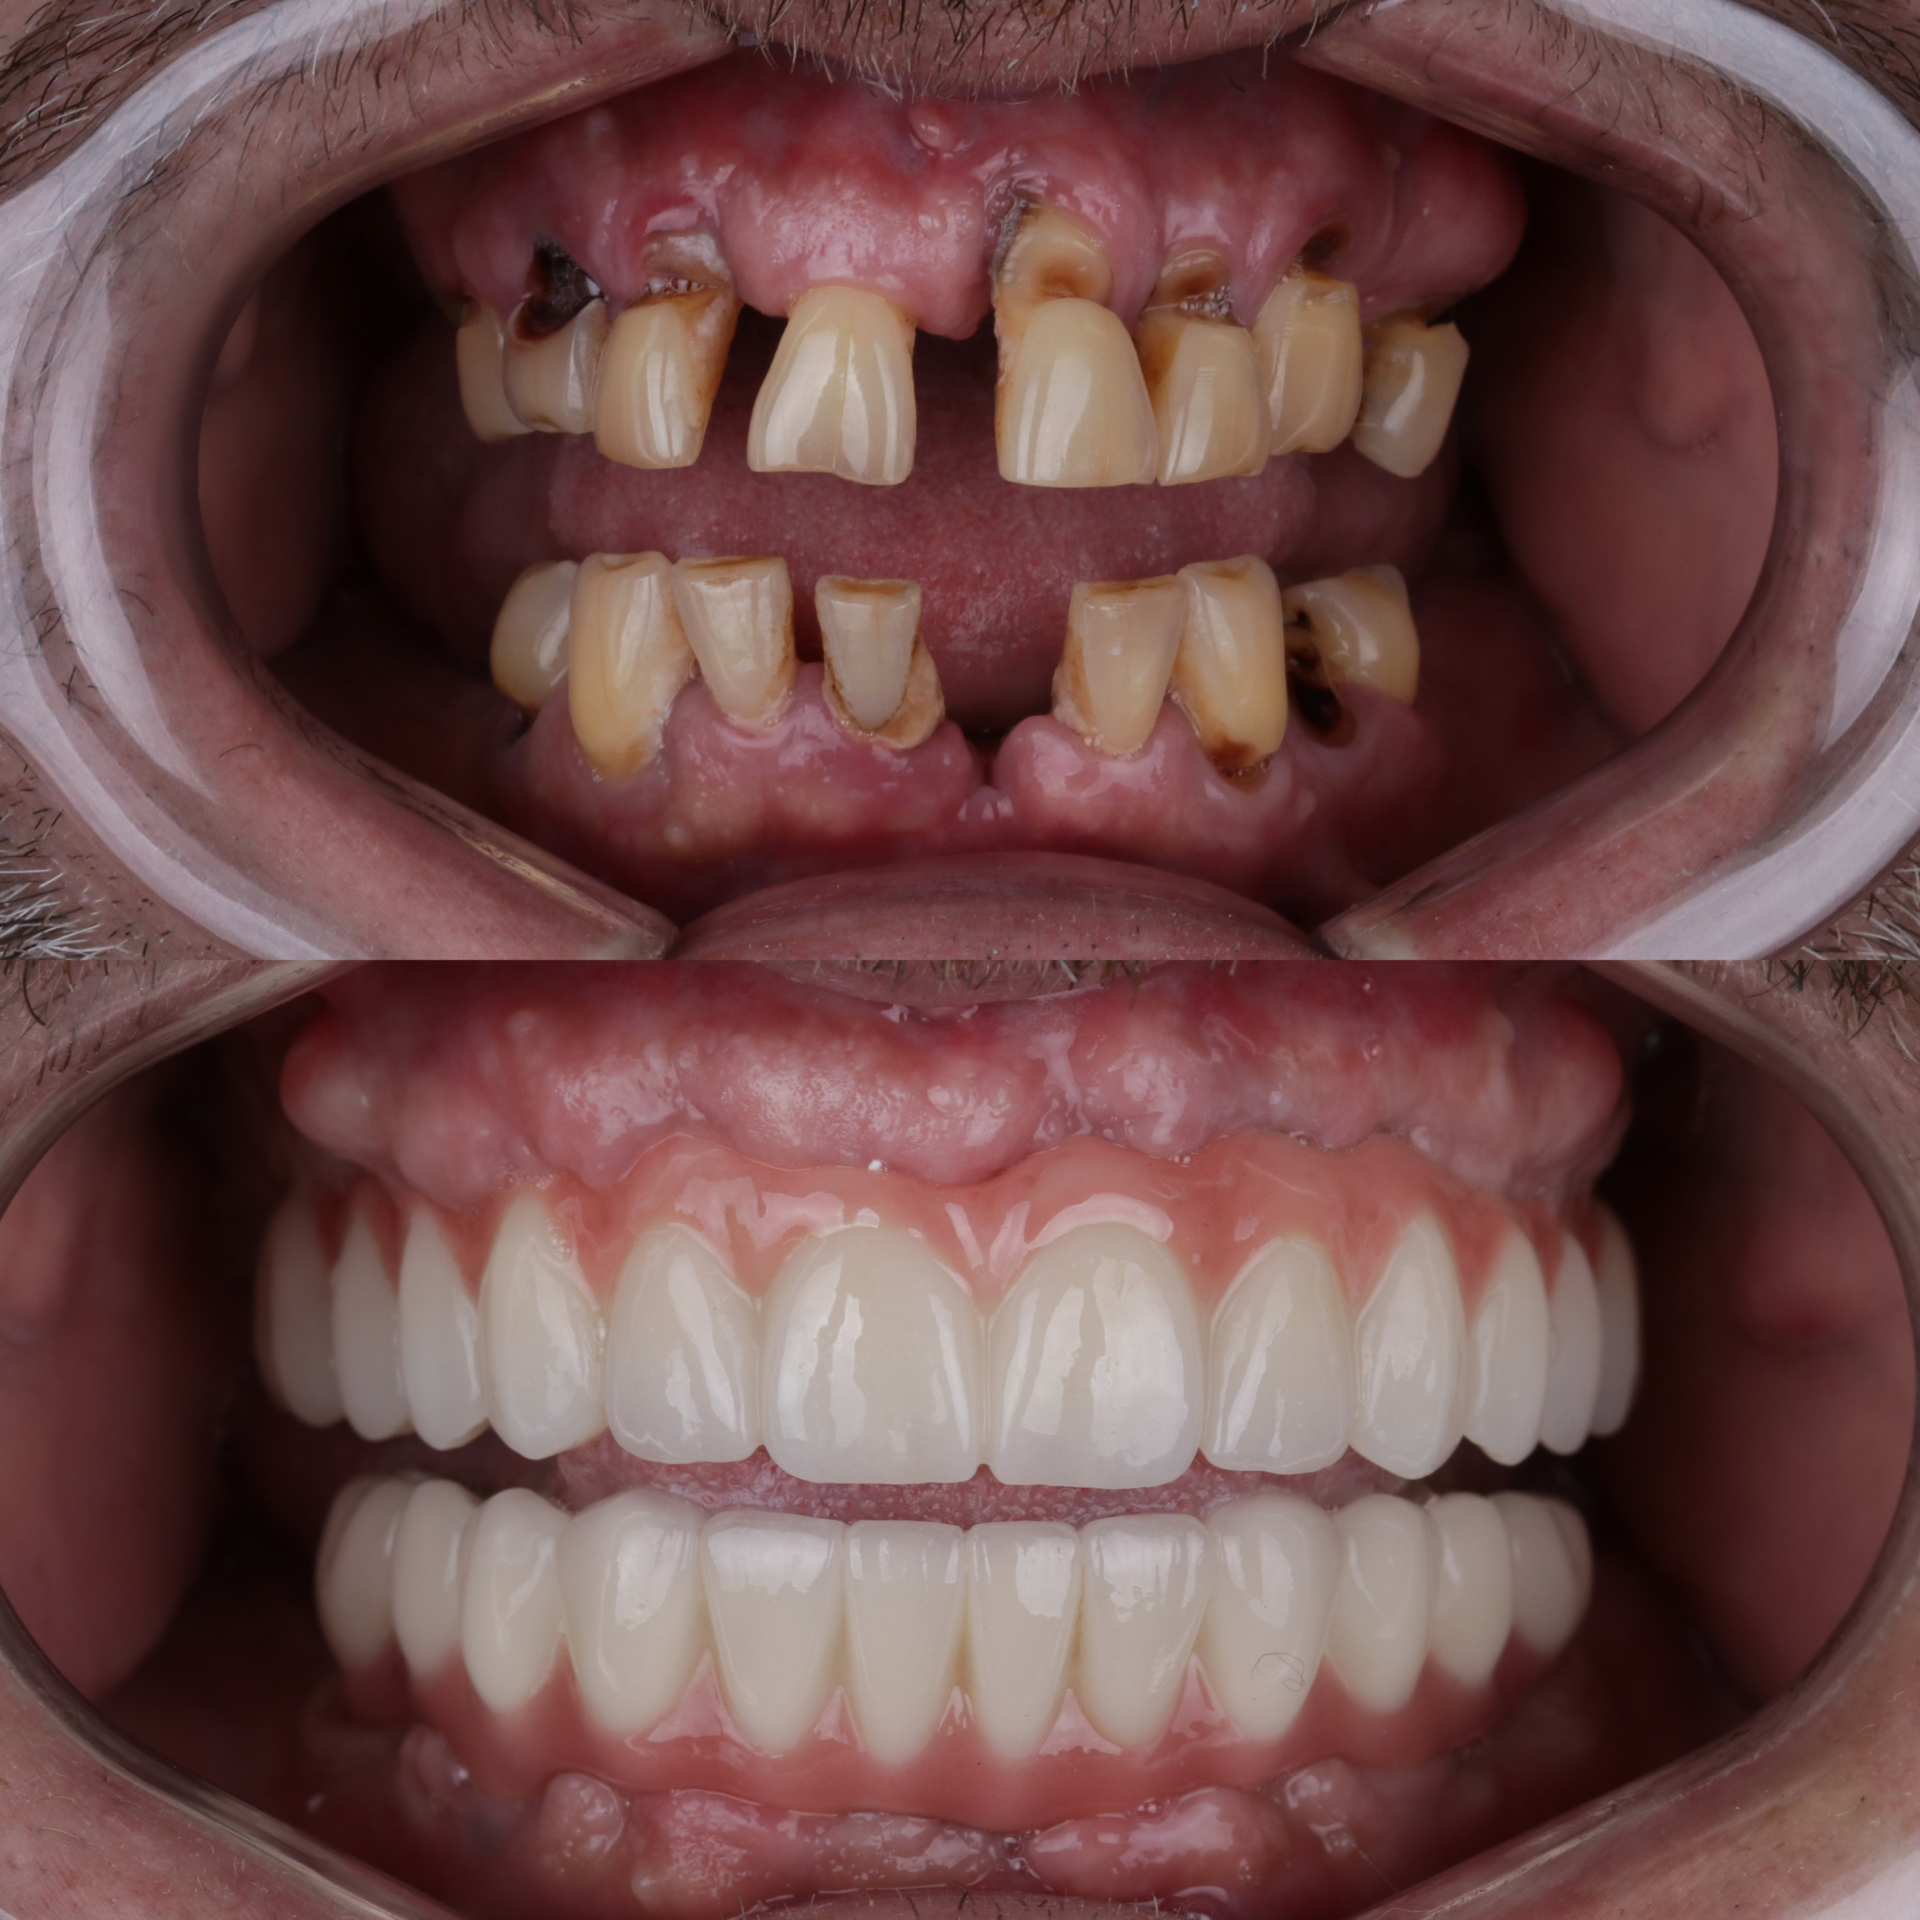

Клинический кейс комплексной реабилитации: проведена имплантация с последующим протезированием коронками, установлены коронки во фронтальном участке, виниры на нижние зубы и восстановлена ​​высота прикуса. В результате восстановлена ​​жевательная эффективность, стабилизированный прикус, равномерное распределение нагрузки и эстетическая улыбка.